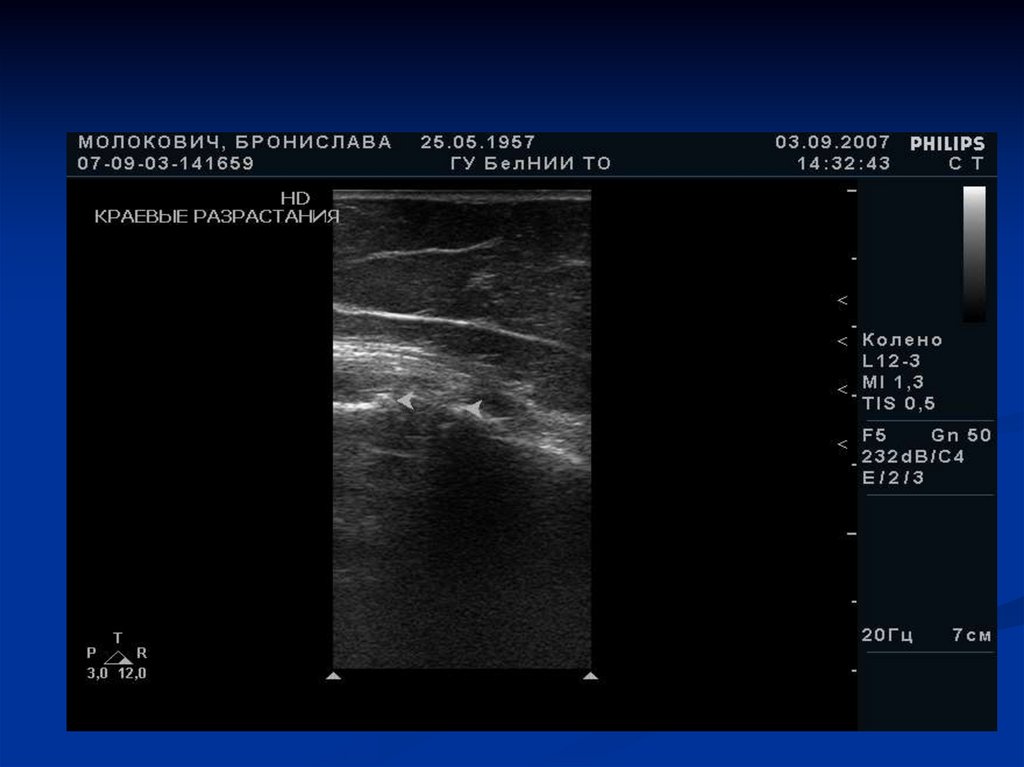

Костные краевые разрастания

Сужение суставной щели и пролабирование мениска